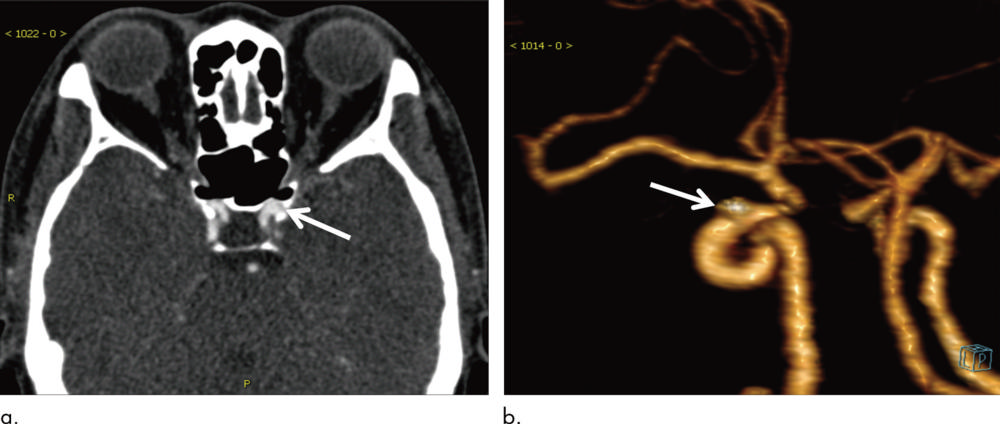

Figure 5. Images in 93-year-old woman with aneurysm 2 mm in maximum diameter located on left posterior cerebral artery (arrow). (a) Axial section head CT angiogram and (b) volume-rendered three-dimensional reconstruction image. Aneurysm was missed on initial report but was successfully detected with algorithm.